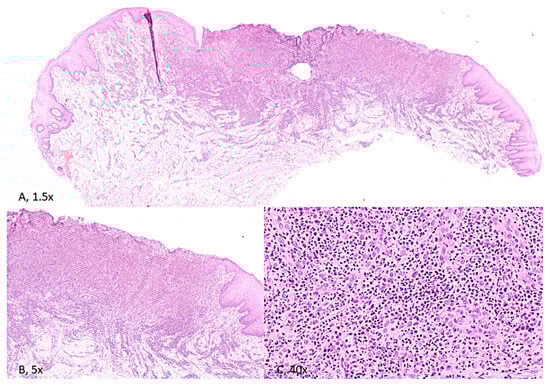

The histopathological examination showed granulation tissue with an infiltration of neutrophil granulocytes and a proportion of eosinophil granulocytes, which can be distinguished by their intense pink cytoplasm and bilobed nuclei. A lymphocyte and plasma cell component was detected, along with blood vessels featuring activated endothelium.

The inflammatory infiltration was found deep within the connective tissue and the underlying muscle layers, which were partially replaced by fibrous tissue. Ulcer borders revealed low-grade epithelial dysplasia of a metaphlogistic nature, associated with lymphocytes exocytosis figures at the basal layer (Figure 3).

Figure 3. (A) [H&E, 1.5× magnification] and (B) [H&E; 5× magnification]. Stratified squamous epithelium of the tongue, widely ulcerated with associated inflammation extending deep into skeletal muscle. (C) [H&E; 40× magnification]. The inflammatory infiltrate consists of acute and chronic inflammatory cells, with scattered eosinophils.